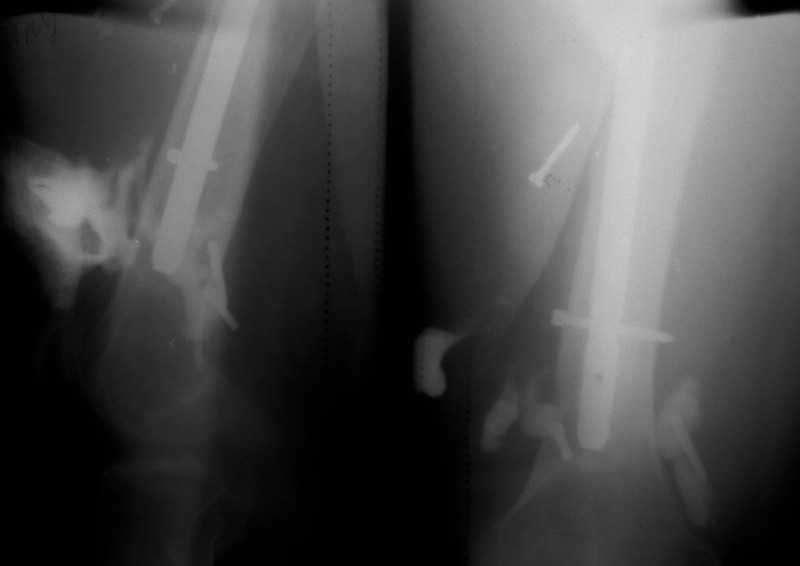

[Ortho] Псевдоартроз бедренной кости, инфекция.

Здравствуйте уважаемые коллеги, прошу Вашего мнения относительно тактики лечения пациента М. 37 лет, рост 170 см. вес 140 кг.

Анамнез: пострадал в рез. ДТП в 2004 году, лечился в одной из районных больниц гдебыл прооперирован DCP.

в 2006 году перелом м/фиксатора с последующим реостеосинтезом стержнем Кюнчера без блокирования.

в 2007 году перелом фиксатора после чего обратился в нашу клинику, где было произведено удаление гвоздя, БИОС L-360 mm D-12 mm с кортико-спонгиозной пластикой, в теч. 6-и мес. больной был под наблюдением динамизация ч-з 2 мес. после чего пациент исчез с поля зрения.

Появился с жалобами на болезненность в месте перелома, укорочение ноги, в течении года поочередно в ягодичной области и н/3 бедра функционирующие свищи.

На данный момент имеем свищ в н\3 бедра, укорочение ноги на 3 см, внешняя ротация.Произведена фистулография, взят посев из свищевого хода.